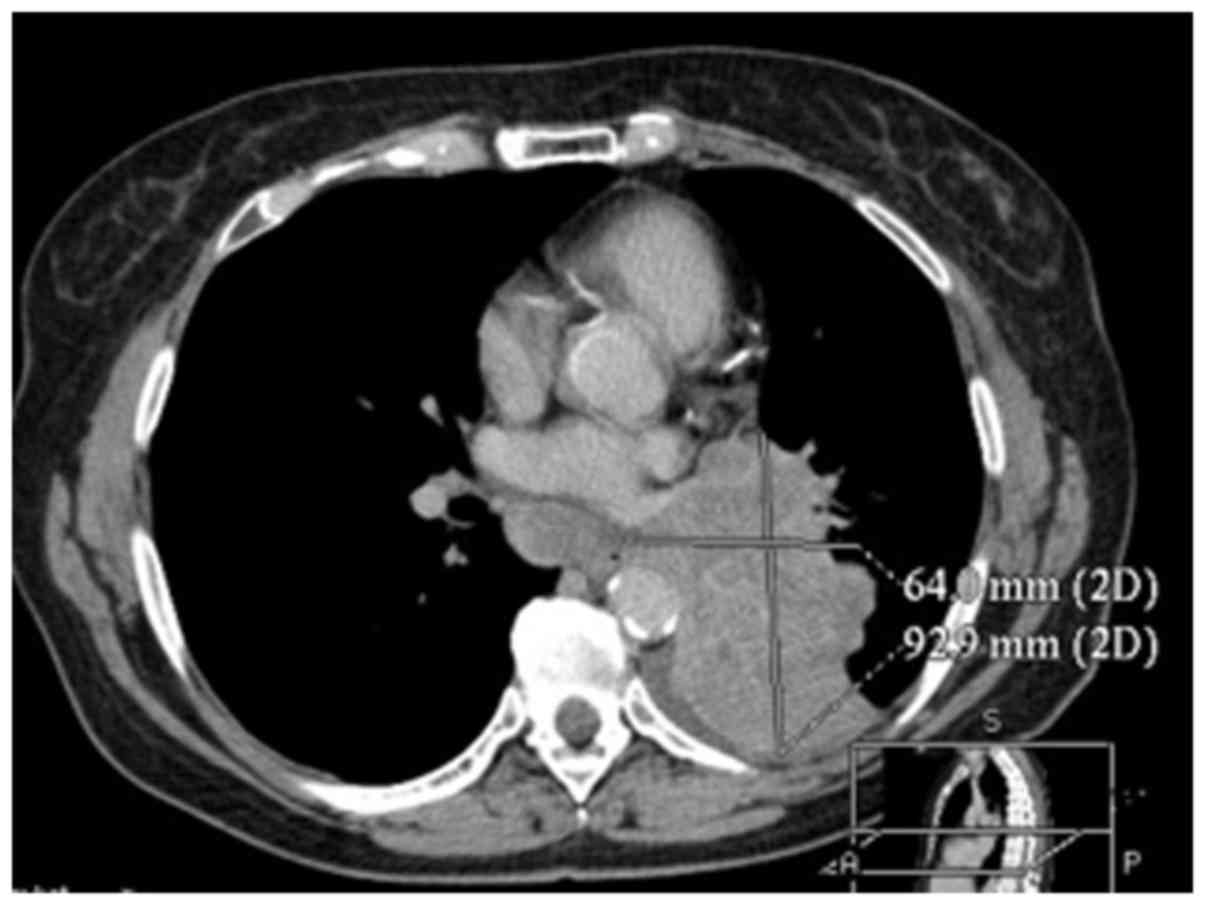

In April 2012, a computed tomography-positron emission tomography scan was performed in order to exclude neoplastic changes in the lymphnodes and metastatic disease. Gamma Knife was then used to treat mediastinal lymphnodes suspected for neoplastic infiltration. Oncological treatment was completed in May 2012 (Figs. 3 and 4). The patient was advised to visit the oncological centre in case of tumour progression detected on annual follow-up examinations.

Figure 3.

Computed tomography imaging showing a suspicious lymphnode in the anterior mediastinum after chemotherapy treatment.